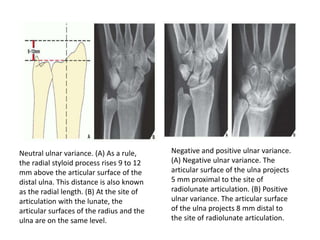

Neutral ulnar variance. (A) As a rule,

the radial styloid process rises 9 to 12

mm above the articular surface of the

distal ulna. This distance is also known

as the radial length. (B) At the site of

articulation with the lunate, the

articular surfaces of the radius and the

ulna are on the same level.

Negative and positive ulnar variance.

(A) Negative ulnar variance. The

articular surface of the ulna projects

5 mm proximal to the site of

radiolunate articulation. (B) Positive

ulnar variance. The articular surface

of the ulna projects 8 mm distal to

the site of radiolunate articulation.